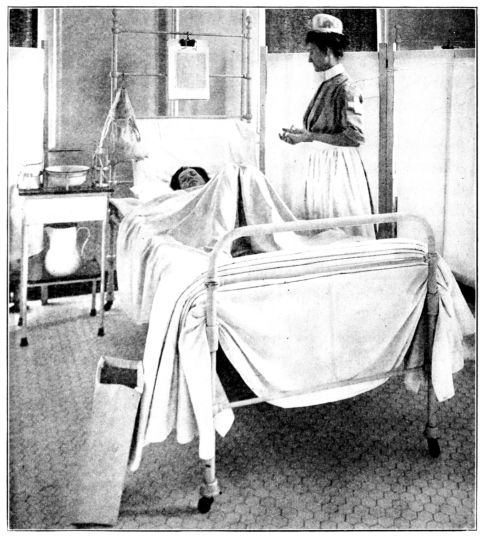

| 117. | Patient draped for postpartum dressing | 336 |